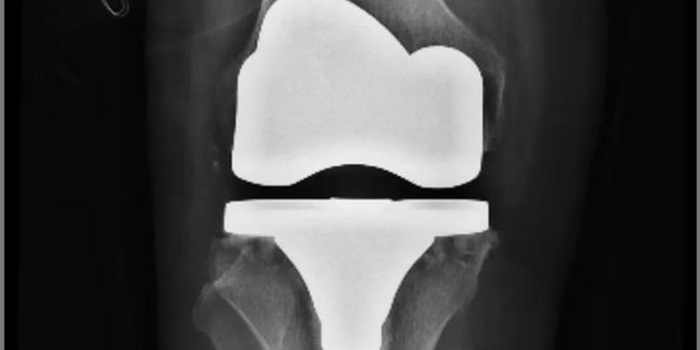

经关节外科门诊系统检查,发现患者右膝关节内翻畸形3°,屈伸活动范围仅10-110°,关节功能严重受限,伴有右膝关节骨性关节炎。为确保手术安全与效果,科室团队秉持严谨态度,为其安排了全面、系统的术前评估。在综合研判其整体健康状况,并确认心肺功能良好、各项指标均符合手术要求后,团队为其量身制定了个性化、精准化的手术治疗方案。

手术在腰硬联合麻醉下进行,由经验丰富的杜明主任主刀,倪守洋医生担任助手。术中探查发现,患者关节滑膜增生水肿,关节软骨已达IV度退变(最严重等级),软骨下骨裸露,边缘骨质增生显著。这对手术团队的病变清理精度、假体安放角度及软组织平衡技术提出了极高要求。

杜主任凭借丰富的经验和娴熟的技术,精准切除了病变的滑膜与增生骨赘,在有限的解剖空间内,成功为患者安装了型号匹配的胫骨与股骨假体。术中即时测试显示,膝关节屈伸活动度可达120度,假体位置精准、稳定性优异,手术顺利完成。